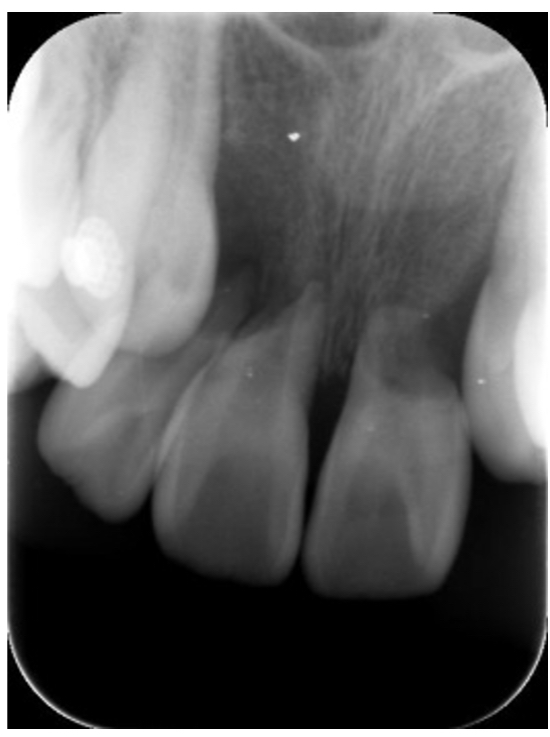

歯の根が短くなる“歯根吸収”とは?

レントゲンで「歯の根が少し短くなっています」と言われると、不安に感じる方も多いかもしれません。

この現象は“歯根吸収(しこんきゅうしゅう)”と呼ばれますが、実際にはほとんどの場合、問題になることはありません。

■ 歯根吸収はどんなときに起こる?

歯根吸収が起こる代表的な場面は、矯正治療中です。

歯を動かす際、根の先に軽い刺激が加わることでごくわずかに吸収が起こることがあります。

しかし、それによって歯が抜けたり弱くなったりすることはありません。

■ まれに起こる特殊なケース

ごく一部のケースとして、子どもの頃に**犬歯が変な方向に埋まっている(埋伏犬歯)**場合、

前歯の根を圧迫して歯根吸収を起こすことがあります。

当院でもこれまで数症例だけ経験がありますが、

早期に発見して矯正治療で方向をコントロールすれば防ぐことが可能です。